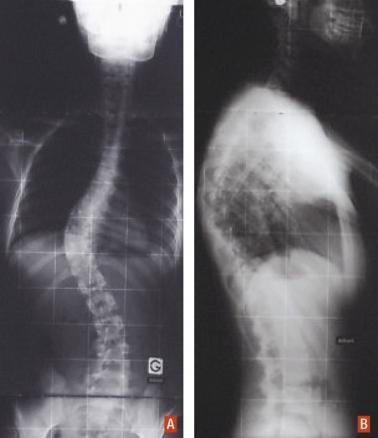

Radiographie du rachis en entier de face (A) et de profil (B) d’une jeune fille ayant une scoliose dorsale droite.